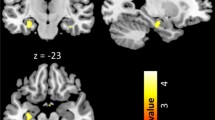

TDI-score was used as a continuous variable to investigate the association between olfactory function and regional gray matter volume. There was a significant positive association between olfactory function and gray matter volume in the left superior OFC (MNI(− 18, 20, − 15), Z = 3.73, k = 193, r = 0.21) (Fig. 2).

Additionally, a multiple regression model including TDI-score as a covariate was used to test the association between olfactory function and regional gray matter volume. As TDI-scores were not normally distributed, the scores were log-transformed. Analysis at p < 0.05 (FWE) at cluster level yielded no significant results. Therefore, we performed an exploratory analysis using p < 0.001 (uncorrected) with a cluster extent threshold of k > 159 voxels, based on the expected number of voxels per cluster (as described in the CAT12 manual).